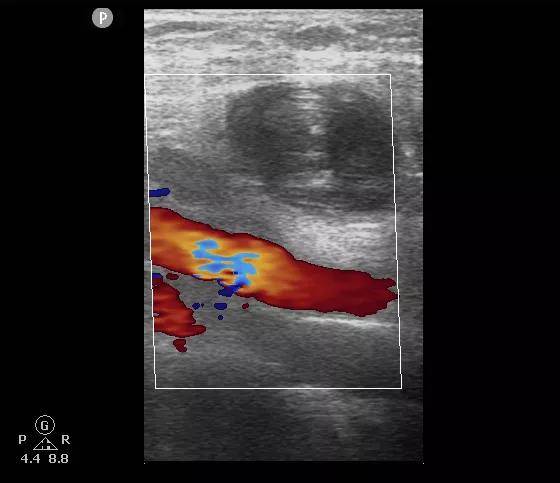

凝血酶注射后:右侧腹股沟区假性动脉瘤内血栓形成 , 其内未见血流信号 。